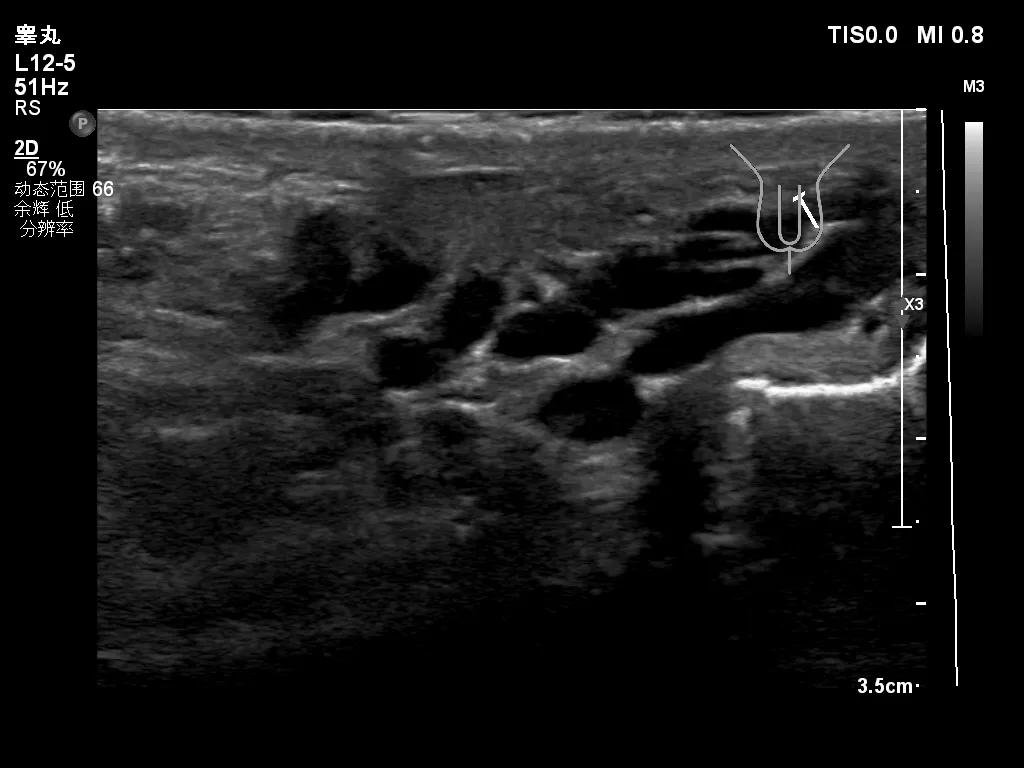

其实我们最关心的是,怎么就可以诊断为精索静脉曲张了,有什么标准,这就需要联合我们的超声检查一起解释了,目前诊断精索静脉曲张需要满足两个条件,1. 精索静脉曲张扩张,内径超过2.0mm;2.乏式实验(其实就是增加腹压的动作),精索静脉内可见大量返流信号(正常情况下,精索静脉瓣膜功能是良好的,乏氏试验后会导致瓣膜关闭,从而阻滞血液返流)。

严重的患者静脉静脉迂曲扩张的非常严重,所以才会摸到阴囊内有疙疙瘩瘩的东西,有时候会摸到一大团,还有触痛。日常接诊中,当患者听到说有精索静脉曲张的时候一般都会很惊讶,一般都会说这个地方还能静脉曲张,因为在我们大家的观念里一说到静脉曲张肯定是下肢,尤其是小腿,会看到好多老年人小腿上突出的如“蚯蚓”状的静脉血管。其实精索区域一样可以发生静脉曲张。

迂曲扩张的精索静脉